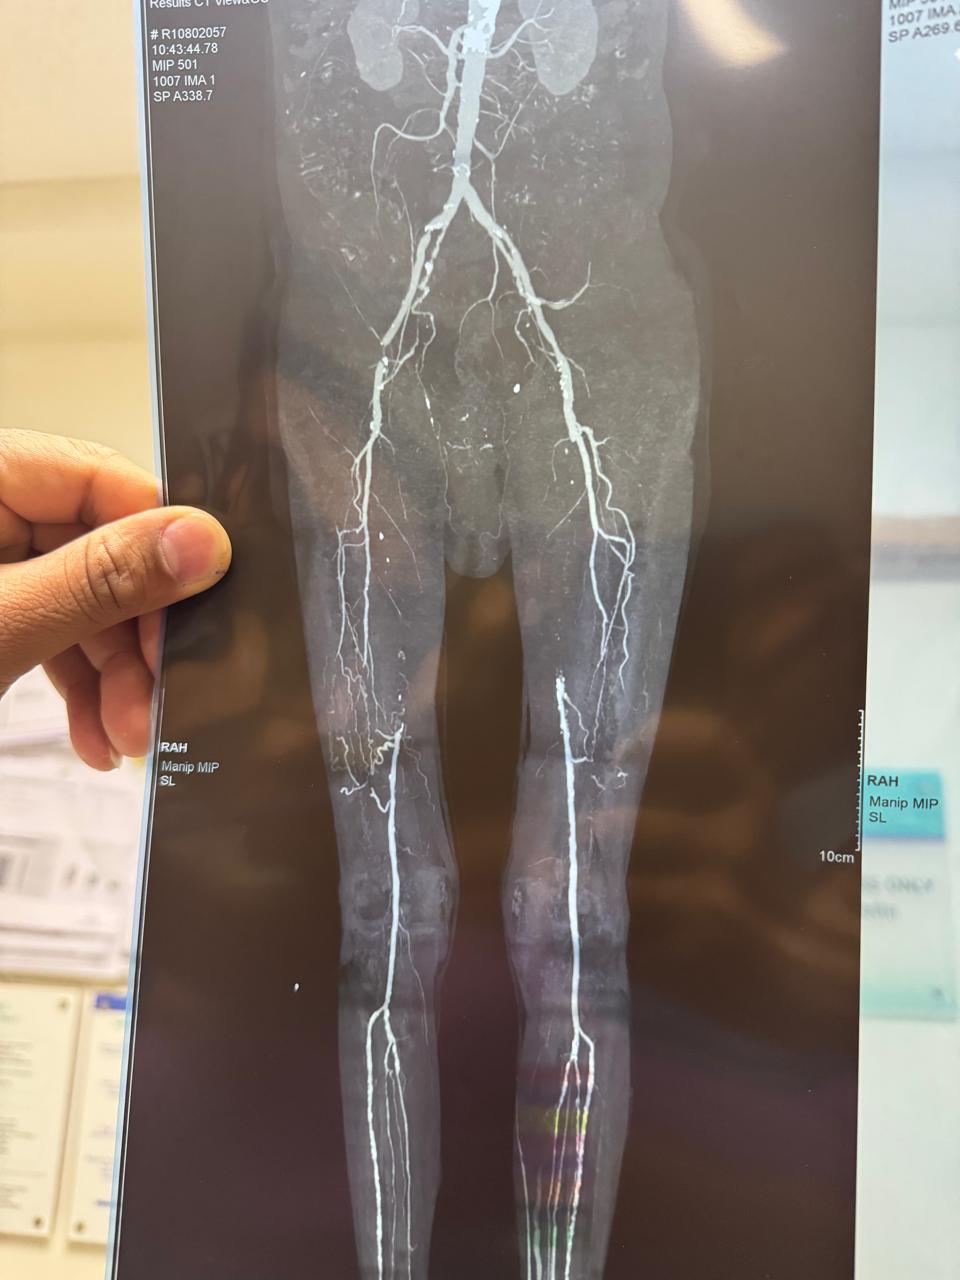

Endovascular Treatment Of Gangrene ( Multi Level Correction)

Right leg critical ischemia grade 5 Hybrid treatment ( right iliac steering + angioplasty then femoro_popliteal bypass) done. Post -op ATA & PTA palpable confirmed on hand Doppler. Patient all symptoms subsides and walk normally.

60 year male patient with uncontroll diabetes , forefoot gangrene and below knee vessel disease,below knee angioplasty and debridement done ,also regular dressing and diabetes uncontrol,wound ready to skin graft